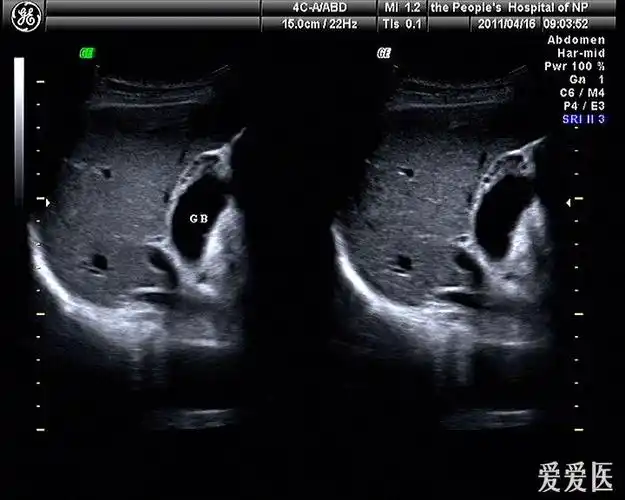

胆囊腺肌症及其它美图分享

胆囊腺肌症可能,请指教 - 超声医学讨论版 - 爱爱医医学论坛

图3-19 胆囊腺肌症(节段型)

青海省康乐医院超声科提醒您一起了解:胆囊腺肌症病变